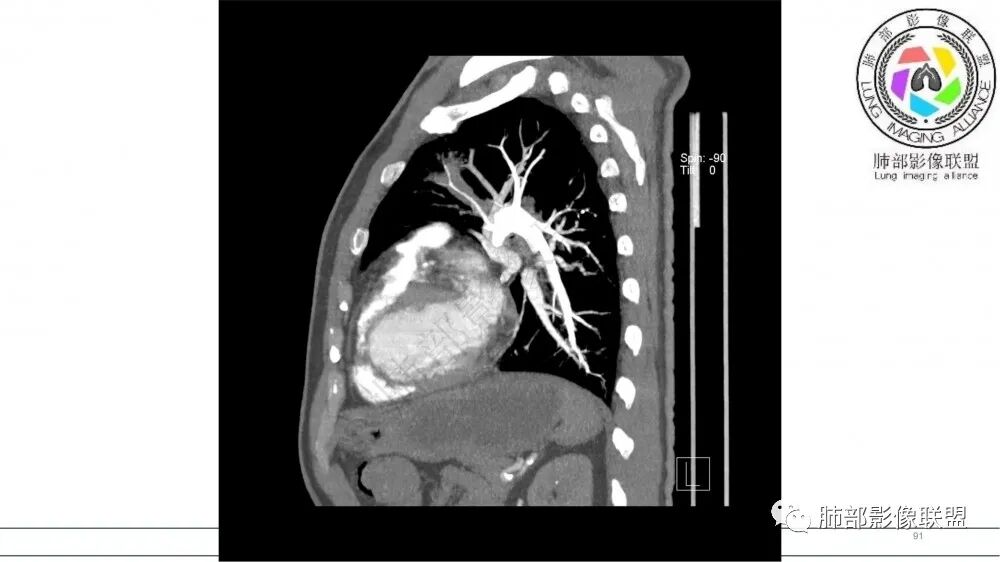

指套征:是影像征象,胸部平片表现为手指状密度增高影,以肺门为中心呈放射状分布,CT显示扩张支气管内低密度黏液栓形成或实性病变,呈管状、树枝状或卵圆形密度增高影;支气管扩张伴近端梗阻时,扩张支气管内部黏液分泌物不能排出而形成。可以伴随远端空气潴留征、阻塞性炎症。

研究报道,中心型 SCLC 经 CT 扫描后通常支气管表现为鼠尾样狭窄,肺门或纵隔肿块明显,由于肿块沿管壁生长表现为顺延支气管形态的不规则形状。病灶相对特征性影像学表现比如鸭蹼状、腊肠状、葫芦状及葡萄状改变,可以出现血管包埋,很少有空洞、空泡,较少引发肺不张,阻塞性炎症成都较轻。与一般肺癌比较,恶性程度高,侵袭力强、病灶很小就容易远处转移!Herzberg 等[19]研究指出,20%以上 SCLC 倍增时间短,预后不良。

文献报道周围型小细胞肺癌发生率为全部小细胞肺癌类型的 35%,近来有学者认为周围型病灶发生率可能更高。CT检查表现为肺实质结节或团块状,密度多较均匀,表现为浅分叶状,边缘光滑、锐利而有时可以酷似良性肿瘤。毛刺征、胸膜凹陷征与空洞、钙化少见,周围血管集束征表现为阴性,出现推移让位等情况。文献报道,增强扫描周围型肿块常表现为“沼泽地样”轻中度强化,增强后密度较低略为均匀,出现小片稍低模糊坏死 。